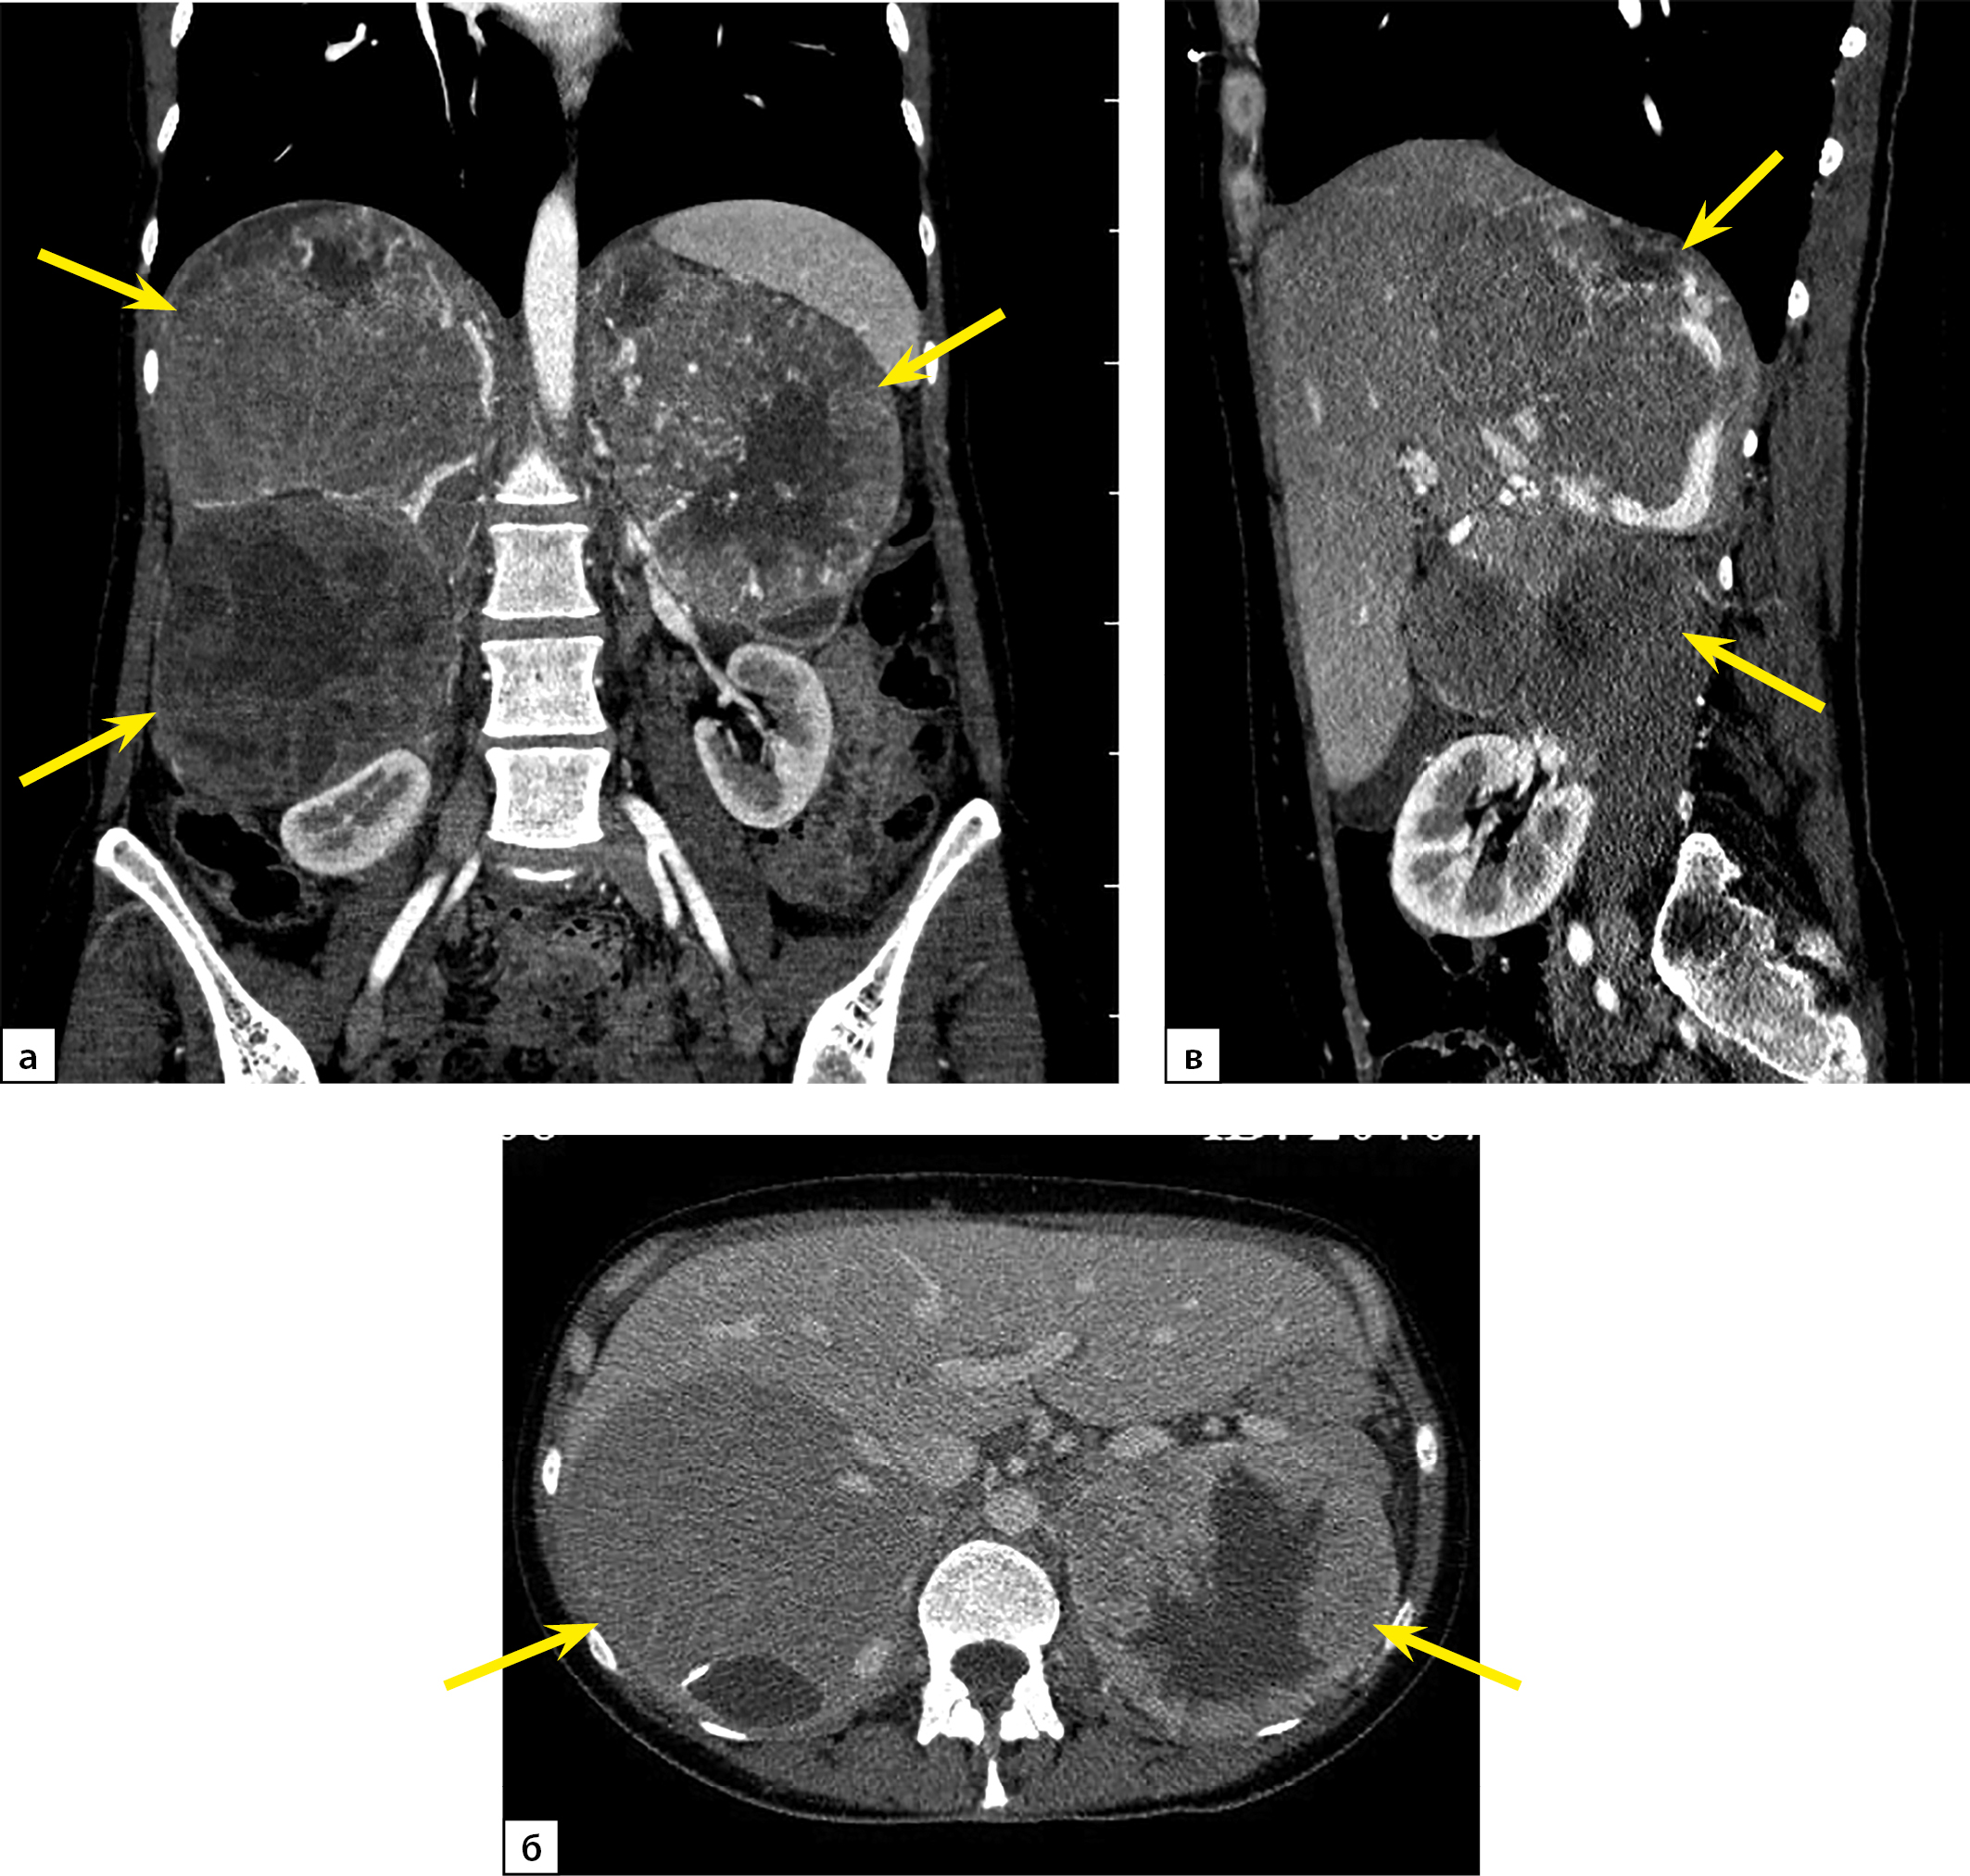

При повторной КТ органов шеи, грудной клетки, брюшной полости и малого таза с болюсным контрастным усилением: КТ-признаков патологических образований органов грудной клетки и шеи не выявлено, визуализируется участок разрежения костной ткани рукоятки грудины, без четких контуров, патологических образований переднего средостения не выявлено, желчный пузырь в размерах не увеличен, в просвете — рентгенконтрастные конкременты до 6 мм в диаметре и плотностью +700 HU. Левый надпочечник увеличен за счет многоузлового образования размерами 110х90х150 мм, плотностью +30 HU. В I фазу накопление контрастного вещества до +60 HU, во II фазу — до +60 HU, через 10 минут плотность образования +50 HU. Правый надпочечник увеличен за счет многоузлового образования размерами 120х120х200 мм, плотностью +30 HU. В I фазу накопление контрастного вещества — до +80 HU, во II фазу — до +75 HU, через 10 минут плотность образования +50 HU. Структура образований обоих надпочечников неоднородная за счет многочисленных зон некроза в центре. Образования обильно васкуляризированы. Надпочечниковые вены широкие, до 10 мм в диаметре (рис. 1). Данных за инвазию окружающих структур, сосудов не получено. Данных за тромбоз нижней полой вены не получено. Лимфатические узлы не увеличены. Очаг остеолитической деструкции в правой лонной кости с наличием мягкотканного компонента размерами 50х40х40 мм (рис. 2).

Рисунок 2. Компьютерная томография органов малого таза с контрастированием: а — артериальная фаза, костное окно, аксиальная плоскость; б — отсроченная фаза, мягкотканное окно, аксиальная плоскость. Стрелками отмечен метастаз феохромоцитомы в лонную кость.

При контроле КТ органов малого таза с контрастированием отмечен рост патологического образования, вызывающего деструкцию верхней и нижней ветвей правой лонной кости, размером 80х57х55 мм (ранее 50х40х40 мм) с пролабацией в полость таза. Выявлена деформация правой стенки мочевого пузыря, прилежащая жировая клетчатка не инфильтрирована.